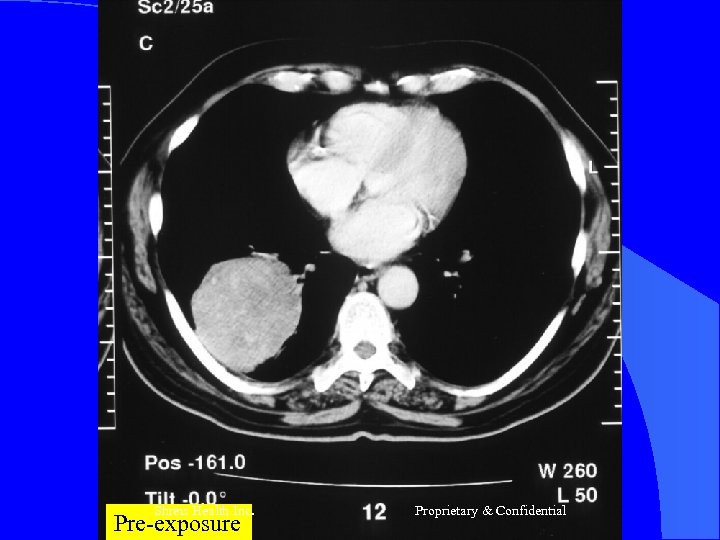

Case- 1 l l l Mr R, 68 yrs Nov-2003 -Ca Lung RLL T 2 N 0 (Adeno ca) Chemo – (Carbo + Eto) 3 # till March 2004 April 2004 – Prog of disease (vide CT) Presented – Cough Hemoptysis - Breathlessness - Pallor - Debility Shreis Health Inc. Proprietary & Confidential

Case 1 RFQMR-1#26/11/2004 – 09/12/2004 2# 24/12/2004 – 07/1/2005 l CT – Jan 2005 – Aug 2005 - Static l Now No Complaints - Energetic - Walks 30 m daily Appetite Good l Shreis Health Inc. Proprietary & Confidential

Shreis Health Inc. Pre-exposure Proprietary & Confidential